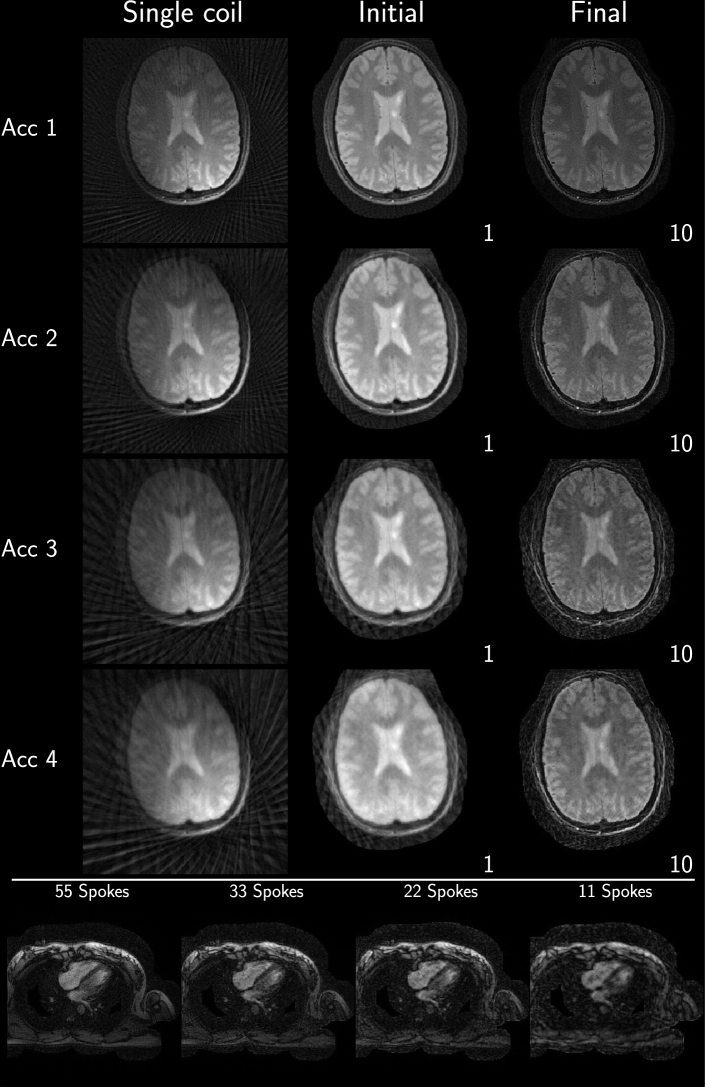

Example reconstruction results for an acceleration factor of 2, showing the image after evaluation of the right-hand-side of equation 3 (Initial) and after convergence of the algorithm (Final), from each submission are given in Figure 2 and Figure 3 for brain and heart data, respectively. All results are displayed with a window width from the minimum to the maximum occurring value in each image. Visually, intensity variations are noticeable owing to the different maximum values, however, contrast between different tissue seems to be similar in all submissions. Some submissions also use different FOVs for the brain (Eindhoven - no cropping, ETH - cropped to 340x340, Stanford - cropped asymmetrical to 300x300 ) compared to the others or different matrix sizes in the same FOV (USC - 256x256 and Utah - 512x512). No major structural differences are observable in the reconstruction except for the case of Eindhoven. The brain reconstruction from KI did neither use Tikhonov regularization nor early stopping, and the k-space was not filtered, resulting in a noisy appearance compared to other submissions. In addition, it shows a slight rotation to the left.

Refer to caption

Figure 4: Consolidated reconstruction results using the Python implementation.